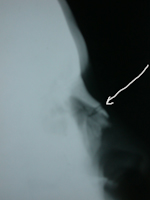

Aspects radiologiques de factures du nez